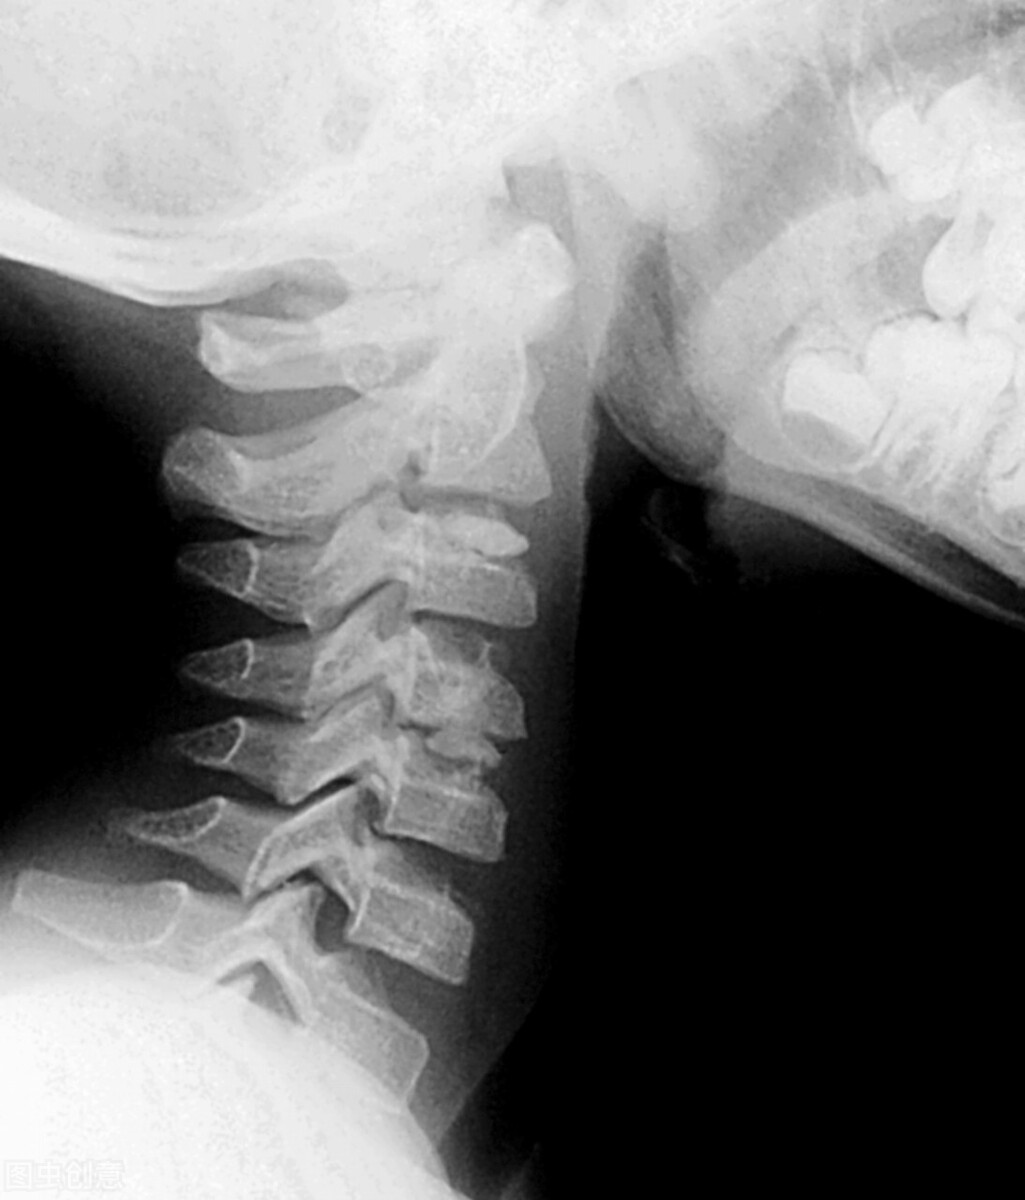

一、颈强直:检查受检者的颈部形态和功能。

颈部运动功能检查:

让受检者直立,做前屈、后仰、侧弯及旋转动作。颈椎中立位(颈直位)时,头向前伸直,下颌内收作为0°。可采用半圆尺或头颈互动测量器测量颈椎活动度。

颈部正常活动度:

(1)前屈: 35-45°

(2)后伸: 35-45°

(3)左右侧弯: 35-45°

(4)旋转: 30°

受检者颈部活动小于上述范围视为不合格。

也可先采用颈椎活动范围的简易测量方法初步评估颈部活动度:

正常时屈颈下颌骨可抵前胸;

后伸时鼻尖与前额连线与体轴垂直;

侧屈肩稍耸耳可触肩。